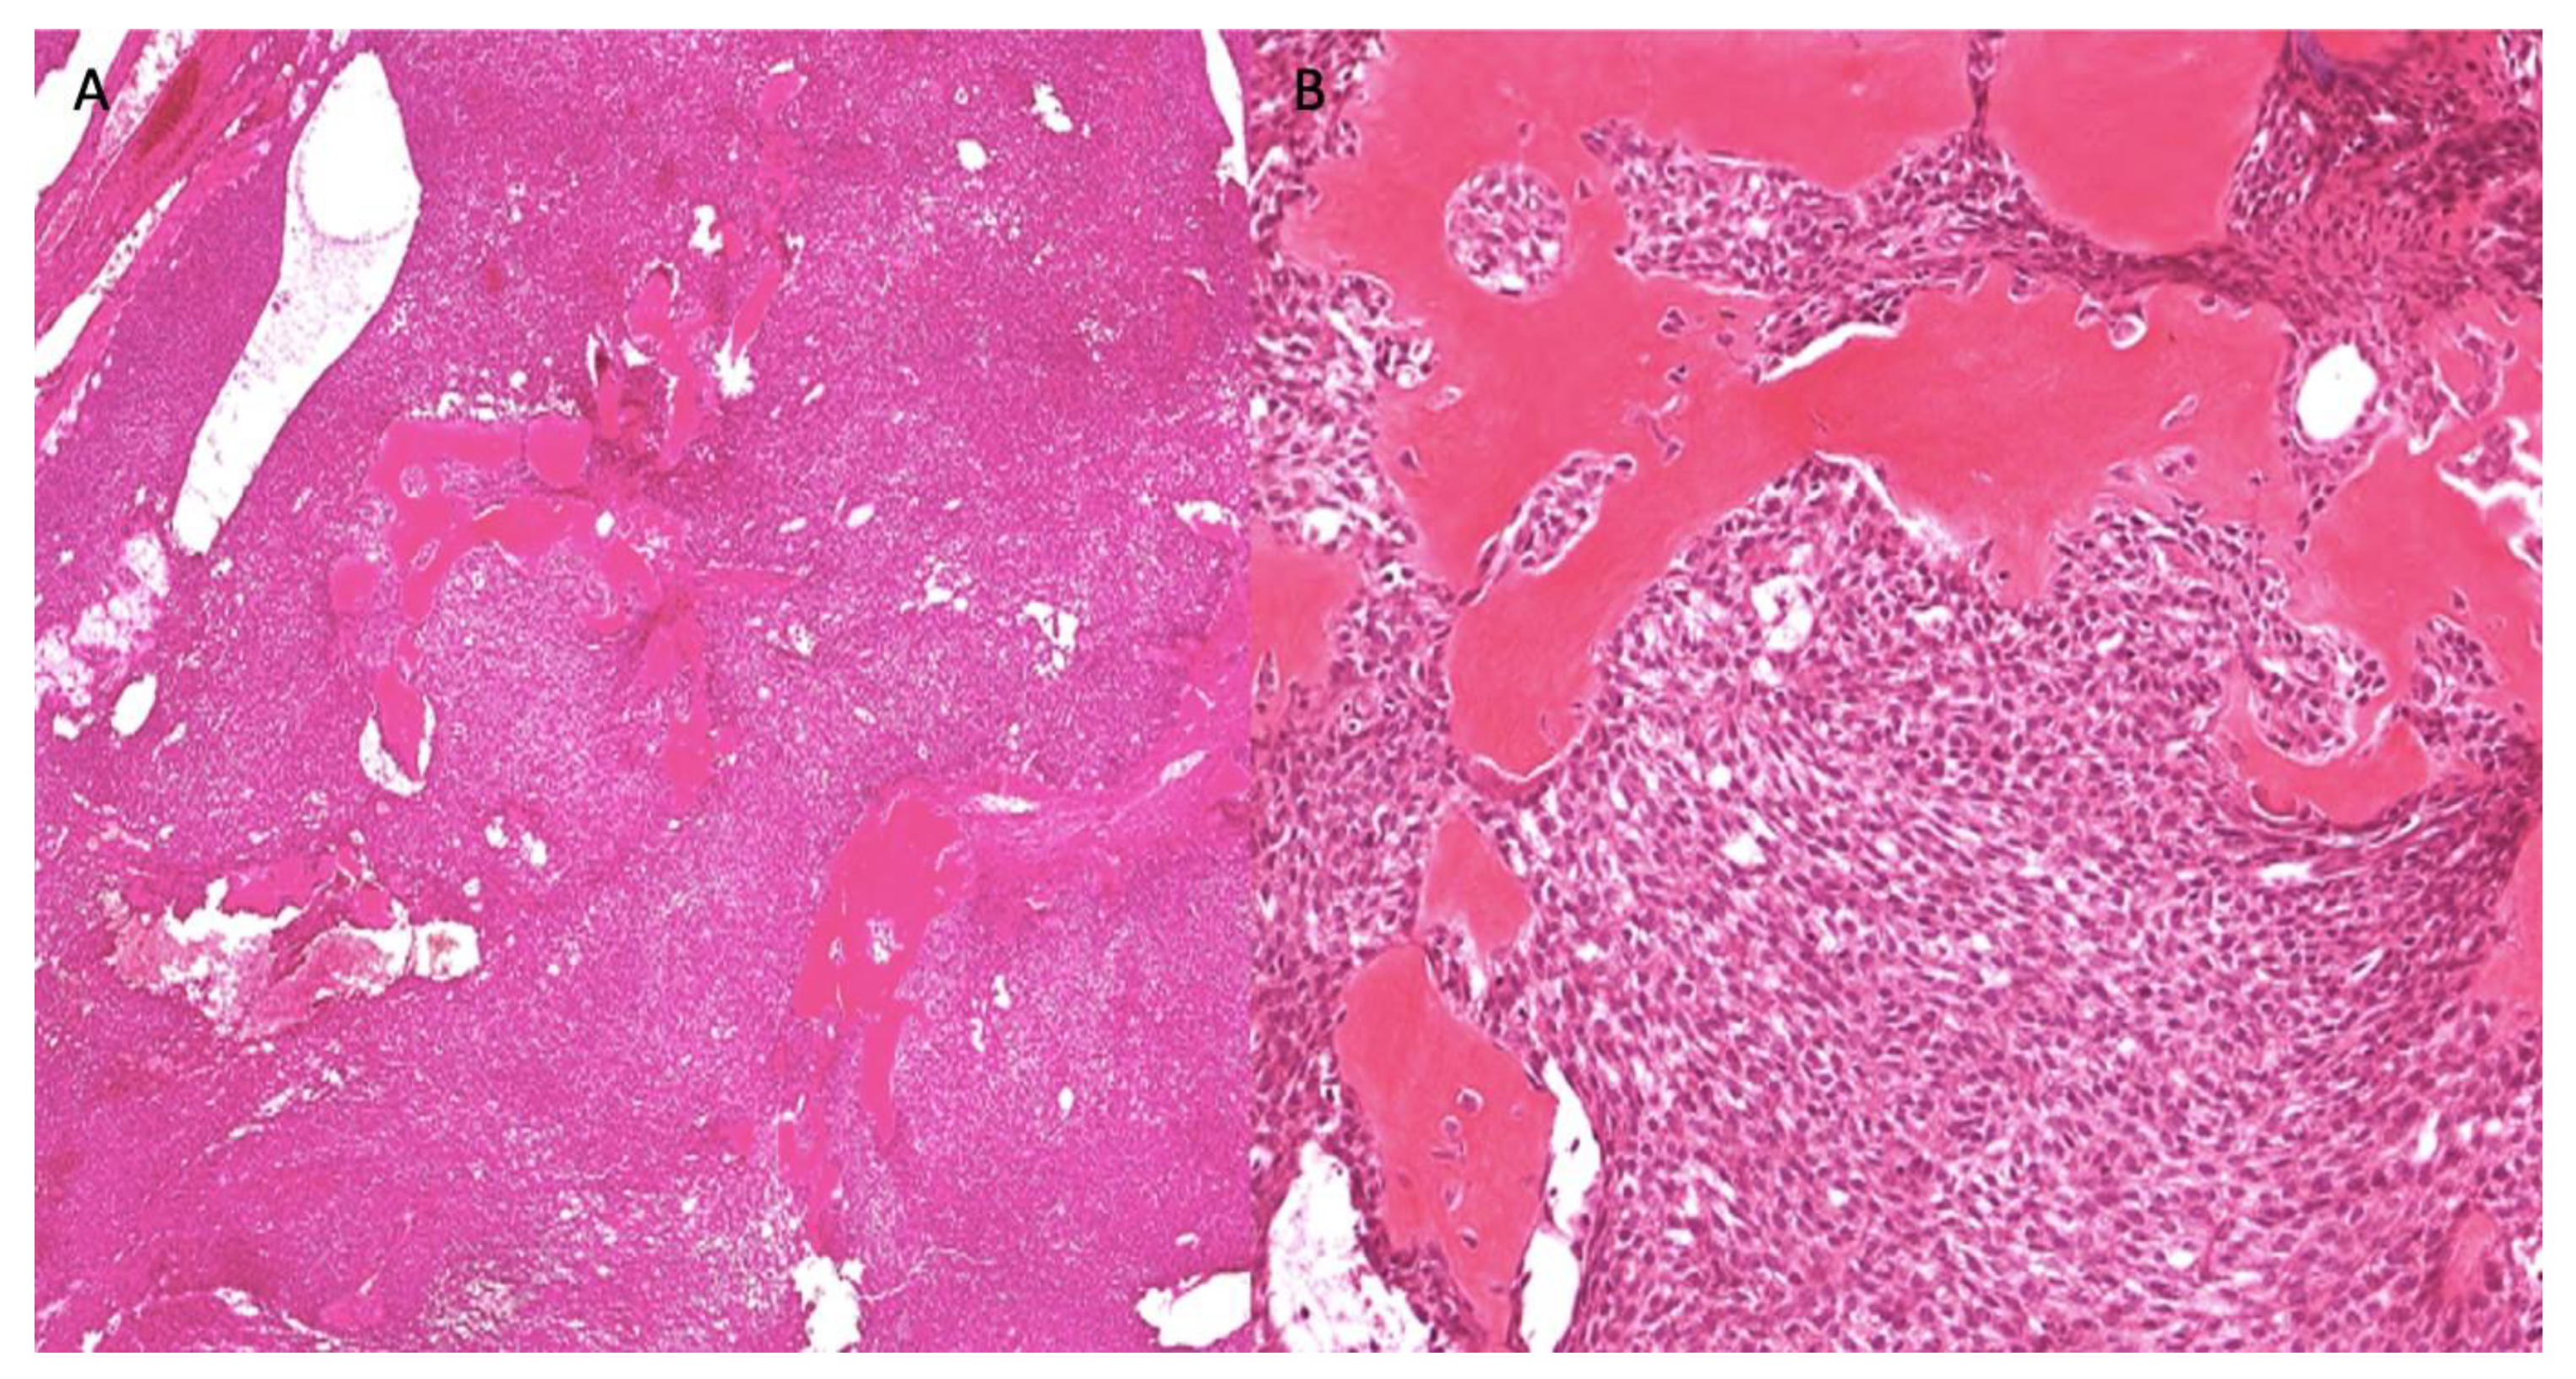

| Morphology | Infiltrative, non-encapsulated malignant neoplastic odontogenic epithelial proliferation with clear cell component in a dense fibrous connective tissue stroma. Neoplastic cells arranged in anastomosing trabeculae. Nuclear hyperchromasia and pleomorphism surrounded by clear, vacuolated cytoplasm. Stroma was hyalinized, densely collagenized, hypocellular, and hypovascular. | Neoplastic odontogenic epithelial proliferation diffusely infiltrated the connective tissue stroma. Neoplastic cells arranged in islands of variable size, trabeculae, and nests. Nuclei were hyperchromatic, central, and pleomorphic surrounded by clear cytoplasm. | Infiltrative odontogenic epithelial neoplasm intermixed with eosinophilic dentinoid matrix. Neoplastic cells arranged in infiltrative, non-encapsulated sheets, cords, and nests of polygonal cells with central hyperchromatic and slightly pleomorphic nuclei surrounded by clear cytoplasm and occasional pale eosinophilic cytoplasm. Occasional mitotic figures were noted. Neoplastic epithelial sheets and cords blended with eosinophilic cellular matrix without cellular rimming consistent with dentinoid deposits. |